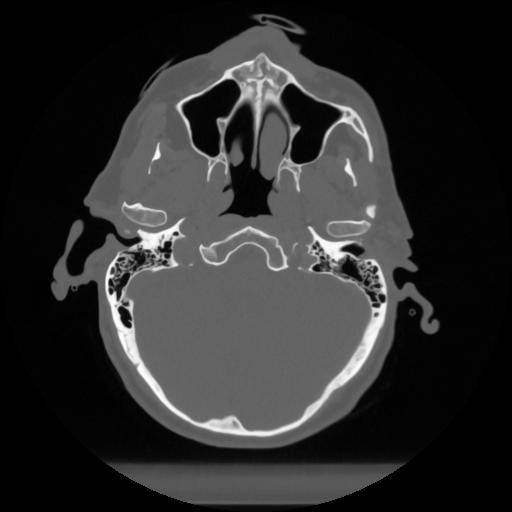

12 P.BLANDAS,,Vol,0.5,P.BLANDAS,,